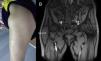

La hipertrofia del músculo tensor de la fascia lata es una entidad clínica poco frecuente que puede simular un tumor de partes blandas. En la mayoría de los pacientes se presenta como una masa anterior palpable en la cara proximal del muslo. La imagen característica en la TC o la RMN es diagnóstica, evitando la realización de biopsia o intervenciones quirúrgicas. En los casos donde se sospeche radiculopatía también es de utilidad el electromiograma. Presentamos un caso clínico y su evolución con tratamiento rehabilitador.

Hypertrophy of the tensor fascia lata muscle is an uncommon clinical entity, which can simulate a soft tissue tumour. In most patients, it presents as a palpable proximal anterior thigh mass. The characteristic appearance on CT or MRI allows a confident diagnosis of muscle hypertrophy to be made, avoiding unnecessary diagnostic biopsy or surgical intervention. In cases with suspected radiculopathy, electromyography is also useful. We present an illustrative case of hypertrophy of the tensor fascia lata muscle and its outcome after rehabilitation treatment.